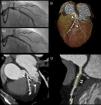

Coronary angiography, showing significant left anterior descending stenosis (A1) and angiographic outcome after placement of a bioabsorbable scaffold (A2). Multislice computed tomography angiography: volume rendering (B) and maximum intensity projection reconstructions (C), revealing the radiopaque indicators (arrows) at the edges of the scaffold. Virtual histology technique showing the non-calcified atherosclerotic plaque (arrows) excluded by the stent (D).

A 68-year-old man with a history of coronary artery disease was admitted with non-ST-elevation myocardial infarction. Coronary angiography revealed 95% stenosis of the proximal left anterior descending artery (Figure 1A1). The patient underwent percutaneous coronary intervention with implantation of a 3.5 mm×18 mm bioabsorbable everolimus-eluting poly(lactic acid) scaffold (Abbott Vascular, Santa Clara, CA) (Figure 1A2). As part of a prospective study, 64-slice CT angiography (SOMATOM Sensation 64 scanner, Siemens, Forchheim, Germany) was performed at the first month follow-up. Radiopaque indicators (arrows) at the edges of the scaffold were the only discernible traces on volume-rendered imaging (Figure 1B) and in maximum intensity projection reconstructions (Figure 1C).

Virtual histology (Aquarius workstation, TeraRecon Inc., San Mateo, CA) showed the non-calcified atherosclerotic plaque (arrows) excluded by the stent (Figure 1D). Cross-sectional in-stent lumen areas were measured, with a minimal lumen area of 5.54 mm2. No significant lumen loss was detected.